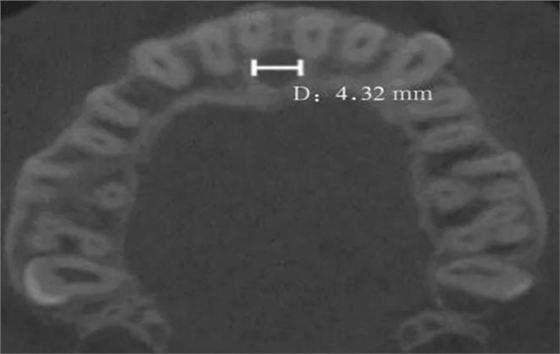

(2)水平面:以第一次觀察到完整的切牙孔形態(tài)的平面作為觀測(cè)平面(圖4)。

D:切牙孔橫徑。

圖 4 切牙孔橫徑測(cè)量方法

Fig 4 Measurements oftransverse diameter of nasopalatine canal